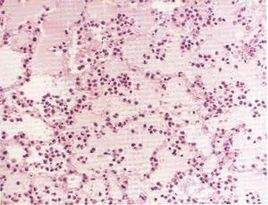

蛋白尿和血尿本品的毒性較慶大黴素和卡那黴素輕,不良反應發生率約2%~3%。臨床套用後少數患者可出現血尿素氮及轉氨酶輕度增高,偶有耳鳴、聽力暫時減退、蛋白尿、血尿、發熱、頭痛、麻木、食慾減退、腹瀉、皮疹等。肌注處疼痛較多,但一般可以忍受。

敗血病檢查血象:白細胞總數大多顯著增高。

細菌塗片:膿液、腦脊液、胸腹水、瘀點等直接塗片檢查,也可檢出病原菌,對敗血症的快速診斷有一定的參考價值。